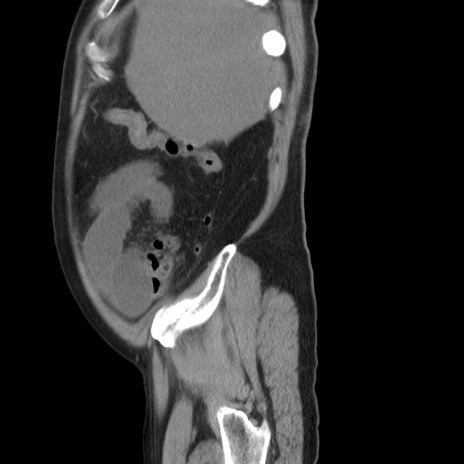

症例20(矢状断像)

【症例】 60歳代男性

【主訴】 腹部膨満、嘔吐

【現病歴】5日前頃より倦怠感を認め食事量減少し4日前の朝嘔吐、食事摂取困難となった。 3日前近医受診し点滴施行され整腸剤などを処方された。 当日他院を受診し、腹部膨満著明、炎症反応の上昇(CRP10.8、WBC11200)あり、紹介受診となる。

【身体所見】 意識JCS1 受け答えがはっきりしないBP 111/57mHg、 P 67bpm、、BT35.2°C、SpO2 97%(RA)、 腹部:膨隆、打診で鼓音あり、全体的に圧痛有り、腸蠕動音(-)、反跳痛ははっきりせず。

【データ】WBC 11400、CRP 14.20